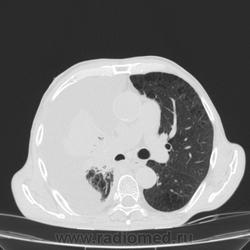

Пожилой мужчина, лечился по н/д правостороннней пневмонии в терап/отделении. Жалобы на одышку, кашель. По результатам Р-контроля после лечения направлен на КТ легких с диагнозом: плеврит справа, распад? В корне правого легкого вижу объёмное образование, с распадом. Смущают размеры плеврита,очень много жидкости, почти до 3 ребра. Анализы крови спокойные- L4,0-6,6, СОЭ 12-16мм. Неужто ТБС, отсев бы был при таком огромном поражении. В посеве мокроты-100% высев клебсиэллы пневмоние. Мокрота на общий анализ в работе-собирает с трудом, изза отсутствия мокроты. Плевральную пункцию еще не проводили. Н азначила бронхоскопию и плеврал пункцию. Как думаете, уважаемые коллеги, это онкопроцесс или тбс распад?

Самое интересное забыла показать- может это 100% навеет на мысль об опухолевом процессе, остеолитическая деструкция позвонка?

По-моему там и слева лимфаденопатия корня легкого, гидроторакс туберкулезной этиологии редко у пожилых бывает

Коллеги, распада там нет, это вас медиастинальное окно подвело. В грудине тоже все в порядке. Да и компрессия позвонка "старая".

Рак.

Небольшое количество увеличенных лимфоузлов, и те - не сказать, чтоб были очень крупными. От эмпиемы до онкологии... Умеренное количество жидкости в перикарде, толщиной слоя до 13-14 мм. При подобной картине не вижу смысла гадать по сжатому лёгкому, пишу так: массивный выпот справа, около 2500 мл, диафрагма оттеснена жидкостью каудально, печень (!!!) смещена каудально и вправо. Легкое справа значительно компрессировано жидкостью, оценка проходимости бронхов и состояния легочной паренхимы (кроме имеющейся эмфиземы) практически невозможна. Необходима пункция плевральной полости справа (цитология, ВК, посев на микрофлору и проч), КТ-контроль после эвакуации жидкости.